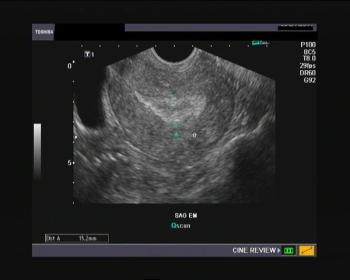

The diagnosis of uterine and/or tubal pathology as causes of female infertility represents a fundamental step in the evaluation of the infertile couple. Apart from the invasive diagnostic procedures, several others diagnostic techniques useful to the clinical evaluation of the uterine cavity and tubal anatomy are: transvaginal sonography (TVS), hysterosalpingography (HSG), hysteroscopy and hydrosonography (HDS) and laparoscopy.